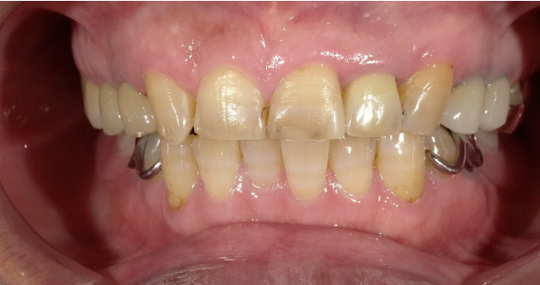

年齢:50代女性

治療内容:左上真ん中から2番目の歯で、他院様での修復物不適合で見た目を気にされてご相談を受けました。e.maxクラウンの審美修復で、ご自身の歯に近い自然で美しい見た目に仕上がりました。

治療期間/通院回数:3回

費用: e.max クラウン 110,000円 ※2025年7月現在の価格